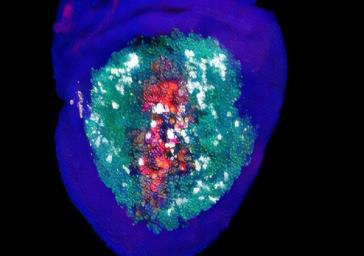

گروهی از محققان دانشگاه ایالتی آریزونا (ASU) هنگام مطالعه نکروز در مگسهای میوه (Drosophila melanogaster)، که به خاطر قابلیتهای بازسازیکنندهشان شناخته میشوند، متوجه نکته غیرمنتظرهای شدند: در لحظات مرگ، سلولهای اطراف سلولهایی که دچار نکروز شدهاند، سیگنالهایی را ارسال میکنند که رشد سلولی را در قسمتهای سالمتر بافت تشویق میکنند.

این کار با تحریک تولید آنزیمهایی به نام کاسپاز انجام میشود. در آپوپتوز، کاسپازها بهعنوان جلاد عمل میکنند، اما زمانی که در فواصل نسبتا طولانی نکروز احضار میشوند، به نظر میرسد که نوع دیگری از کاسپاز باعث بهبودی در سلولهای خاص میشود.

محققان امیدوارند که سلولهای کاسپاز مثبت (NiCP) نشأت گرفته از نکروز که به تازگی کشف شدهاند، بتوانند در مورد بازسازی بافت و ترمیم زخم اطلاعات بیشتری به ما بدهند. با این حال، تنها برخی از سلولهای فعال شده با کاسپاز که به نکروز واکنش نشان میدهند، زنده ماندند. دانستن دلایل این امر گام مهم بعدی خواهد بود.

کلوئه ون هازل (Chloe Van Hazel)، متخصص پژوهشی از دانشگاه ایالتی آریزونا، میگوید: در مجموع، جدیدترین یافتههای ما مدلی را پیشنهاد میکند که در آن آسیبهای نکروز باعث ایجاد فعالیت کاسپاز در سلولهایی با فاصله از سلولهای آسیبدیده میشود.